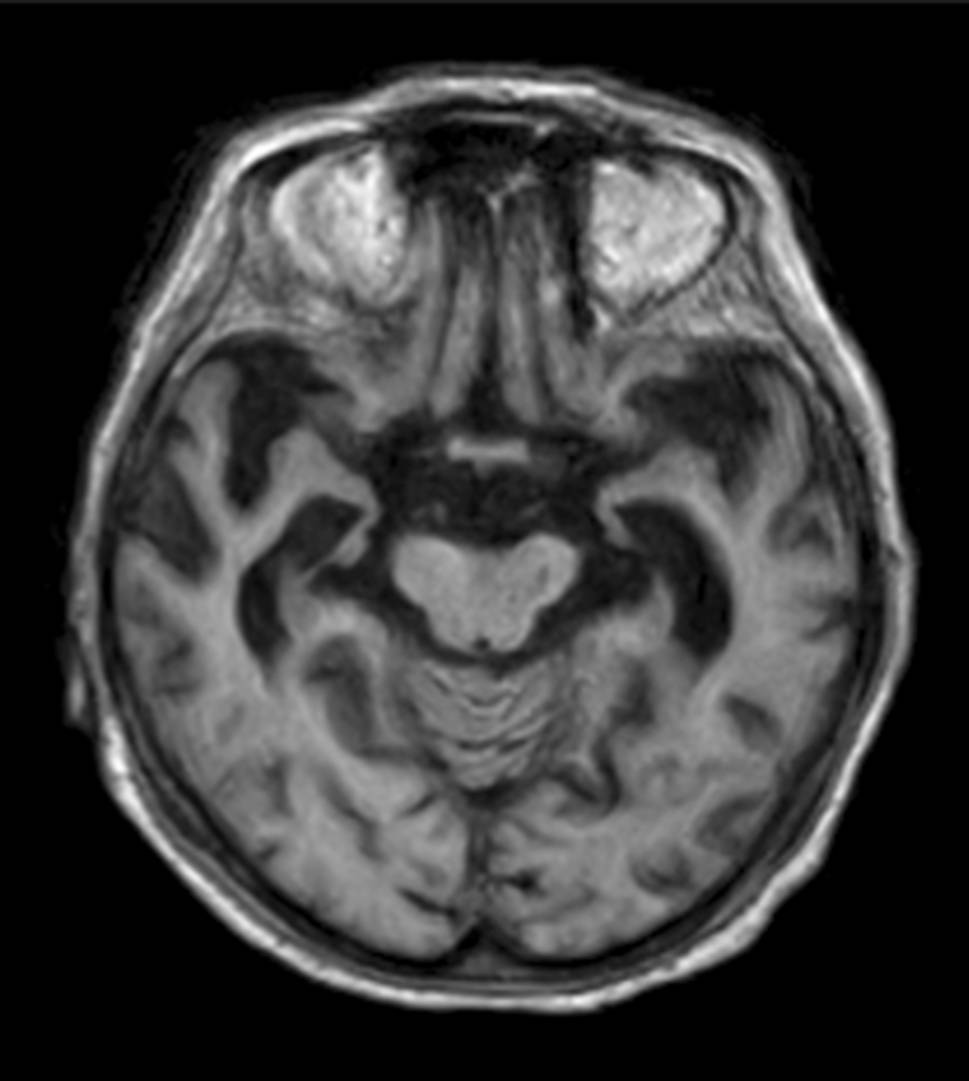

Another special subgroup of vascular disease is CADASIL, which is a hereditary vasculopathy based on mutations in the NOTCH3 gene [16, 17]. Patients with CADASIL show extensive white matter hyperintensities, lacunar infarctions, and hemorrhage mainly in the insulae and the anterior temporal lobes (illustrated in Fig. 12) [18].

Fig. 12

CADASIL. A 50-year-old female patient with CADASIL who presented with characteristic extensive white matter hyperintensities, particularly bilateral temporal, depicted on axial (a, b) and coronal (c) T2-weighted images

Bild vergrößern